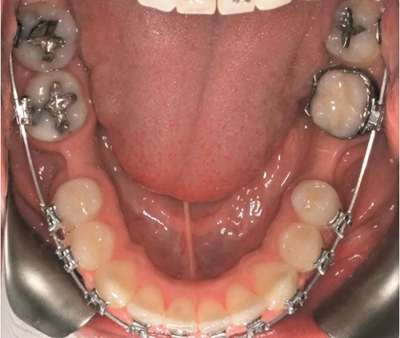

圖1b.臨床檢查顯示牙槽嵴萎縮,右下第一磨牙的無牙間隙近遠中距離為6.5mm,左下第一磨牙為9mm

為患者采用了直絲弓自鎖托槽(Damon,Ormco)。最開始用0.016×0.025 英寸的不銹鋼弓絲(Damon,Ormco)進行矯正和排齊,歷時7 個月。在磨牙直立加力之前,下頜第一磨牙位點無牙區(qū)的近遠中距離為右側(cè)6.5mm、左側(cè)9mm(圖1)。磨牙遠移和直立的目標是實現(xiàn)雙側(cè)最終冠修復體的近遠中直徑達到10mm。右側(cè)第一磨牙位點的大小差異比左側(cè)更大,牙槽嵴吸收更多,頰舌徑約4.5mm(圖2)。在詳細解釋同期牙槽嵴增量和加速磨牙直立程序后,患者選擇右側(cè)位點進行種植治療。因此,為了加速該位點的空間建立,圍繞第二磨牙行選擇性去皮質(zhì)術(shù)和同期牙槽嵴增量術(shù)。